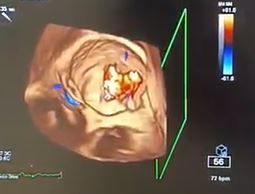

In particolare mi occupo di diagnosi e gestione delle principali valvulopatie mediante esecuzione di ecocardiografia di primo e secondo livello (ecocardiografia transesofagea con particolare focus sull'imaging 3D) e del follow-up dei pazienti presso un ambulatorio dedicato.

Inoltre mi occupo di ecocardiografia con mezzo di contrasto e di ecocardiografia da stress (sia con l'utilizzo di farmaci che con stress fisico-lettoergometro).